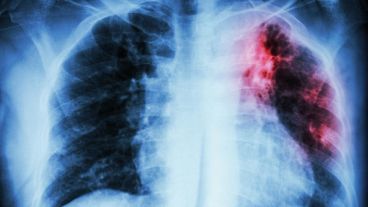

No obstante, esta enfermedad que afecta a los pulmones y se transmite por la expectoración de pequeñas partículas, sigue siendo una de las 10 primeras causas de muerte en el mundo, indicaron en el informe.